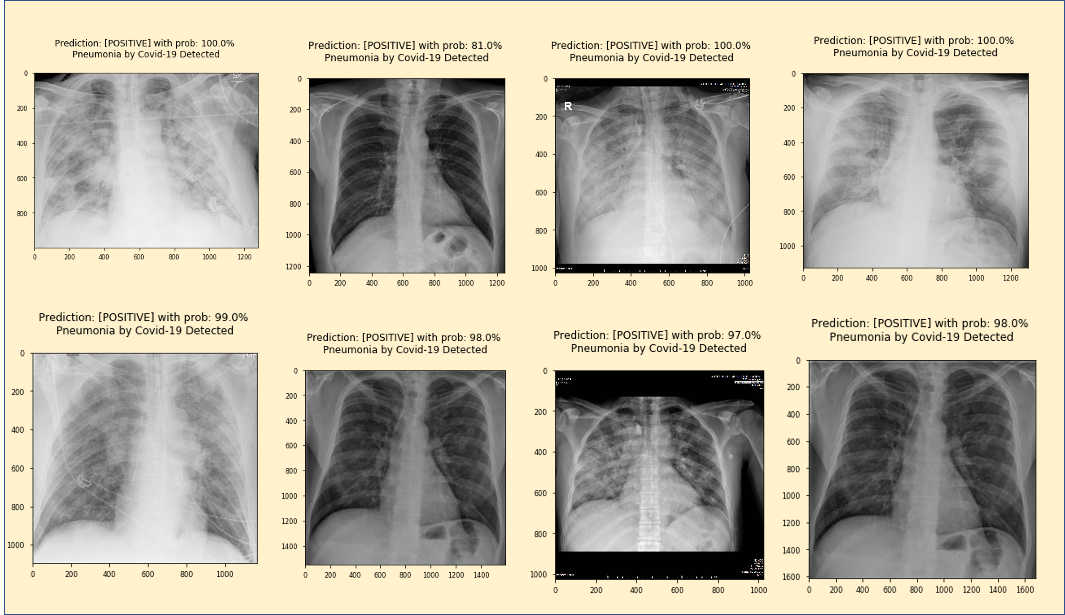

该项目的灵感来源于UFRRJ(里约热内卢联邦大学)开发的X光COVID-19项目。UFRRJ的XRayCovid-19是一个正在开发的项目,在诊断过程中使用人工智能辅助健康系统处理COVID-19。该工具的特点是易用、响应时间快和结果的有效性高,我希望将这些特点扩展到本教程第4部分开发的Web应用程序中。下面是诊断结果之一的打印屏幕(使用了Covid-19数据集1图像之一):

在Notebook上,此函数将显示以下结果:

通过更改其余7个图像的imagePath值,我们获得以下结果:

所有图像均呈阳性,确认100%灵敏度。